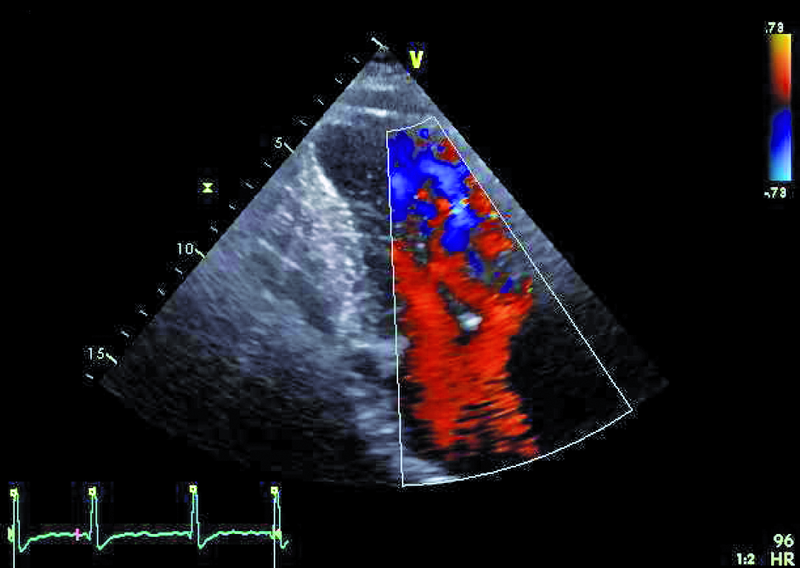

Operację Fontana, będącą rodzajem zabiegu paliatywnego, wykonuje się w celu korekcji zaburzeń hemodynamicznych towarzyszących wspólnej komorze. Celem operacji jest zmniejszenie przeciążenia objętościowego komory, ponieważ otrzymuje ona napływ zarówno z żył płucnych, jak i systemowych. Jest wiele rodzajów serca jednokomorowego. Najczęściej spotyka się zespół z atrezją trójdzielną, niedorozwojem lewej komory, zarośnięciem tętnicy płucnej, dwunapływową komorą lewą, dwuodpływową komorą lewą lub prawą. W podanym przykładzie można wyróżnić dwie zastawki przedsionkowo-komorowe, a więc krew wpływa do wspólnej komory (anatomicznie lewej) zarówno przez ujście trójdzielne, jak i mitralne, co dowodzi obecności komory dwunapływowej (ryc. 1-4). Celem operacji w tym wypadku było nie tylko oddzielenie spływu z żył systemowych, ale także zwiększenie całkowitej objętości krwi płynącej przez łożysko tętnic płucnych. Jak oceniać echokardiograficznie pacjenta po operacji metodą Fontana? Nie dziwi, że wspólna komora jest powiększona (ryc. 1, 2, 5), przerośnięta (ryc. 1, 2) i wykazuje upośledzoną kurczliwość. Jeśli wykształcone są dwie zastawki przedsionkowo-komorowe, należy ocenić każdą z nich, ponieważ fale zwrotne powodowane przez zastawki mogą zwiększać objętość komory i niekorzystnie wpływać na funkcję kurczliwą mięśnia. Niedomykalność zastawek przedsionkowo-komorowych (w podanym przykładzie umiarkowana [ryc. 5]) może także zwiększać ciśnienie w jamie lewego przedsionka, co zmniejsza konieczny dla wytworzonego zespolenia gradient ciśnień: żyła systemowa – tętnica płucna – lewy przedsionek. Wynikiem zmniejszania się gradientu może być narastanie ciśnienia w kanale Fontana (ryc. 1-3), pojawienie się hepatomegalii, przesięków do jam ciała, zespołu enteropatii z hipoproteinemią. Niemal u wszystkich chorych po operacji Fontana obserwuje się poszerzenie światła żyły głównej dolnej ze zwolnieniem przepływu krwi i zjawiskiem samokontrastowania się. Nie zawsze udaje się precyzyjnie uwidocznić morfologię wykonanego zespolenia. W tym wypadku mieliśmy do czynienia z tzw. starym jego rodzajem, polegającym na bezpośrednim połączeniu prawego przedsionka z pniem tętnicy płucnej bezpośrednio (ryc. 6). Metoda taka (Fontana-Linsa) stosowana była w latach 70. i 80. ubiegłego stulecia. W przypadku ciężkiego upośledzenia funkcji kurczliwej wspólnej komory, braku zwężenia w kanale Fontana i wykluczenia istotnych niedomykalności zastawek przedsionkowo-komorowych postępowaniem z wyboru pozostaje zabieg przeszczepienia serca, do którego chory został zakwalifikowany.